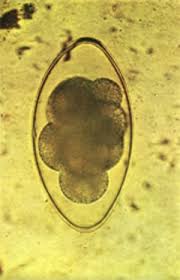

Toxocara canis, Toxocara cati, Toxascaris leonina

Host: canine and felines; Location: small intestine; Common name: canine and felines roundworms; Diagnosed: fecal flotation; Treatment: Vermifuge (Piperazine/Pyrantel), Vermicide (Thiabendazole/Mebendazole)